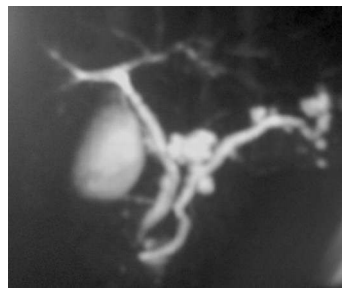

Um paciente de 62 anos de idade, etilista, assintomático, fez exames de ultrassom, que revelaram lesões pancreáticas císticas. Realizou, também, uma colangiopancreatografia, uma ressonância e exames laboratoriais. No exame de sangue, amilase e lipase normais e CEA e Ca19.9 dentro do limite

A imagem acima corresponde ao exame de